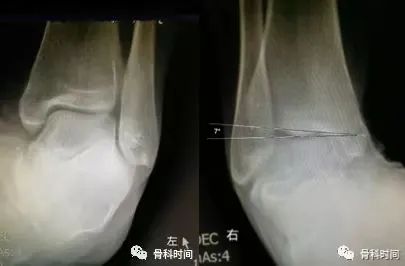

28 岁青年女性,约 2 年前左踝首次发生崴脚,未行外固定处理,近 1 年来左踝间断多次崴脚,双侧踝关节应力正位片测量距骨倾斜角,左侧为 10°,右侧 4°,左侧应力位状态下感疼痛,右侧无不适感,考虑左侧踝关节不稳。